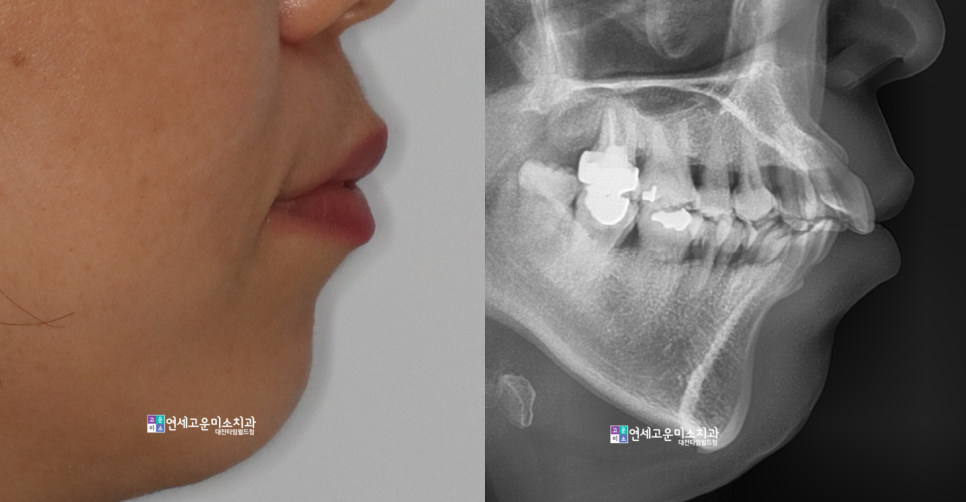

40대 중년의 여성분이셨고

돌출이 꽤 심하셨던 분입니다.

발치치료로 돌출을 해소하면 좋을 것 같은데요

환자분 걱정은 잇몸이 안 좋아서

할 수 있을지 걱정이셨습니다.

치아 상태를 보면 덧니도 심하고

잇몸도 많이 내려간 상태셨습니다

교정 후 옆모습입니다

환자분께서 말씀하셨던 게 아직도

기억에 남는데요. 나는 평생의 한이 돌출입이라

하셨는데요. 만족할 만큼 해소가 되었습니다.